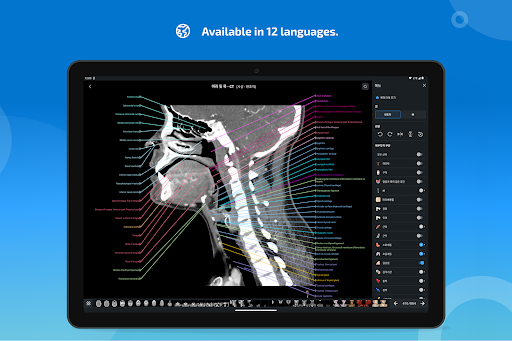

e-Anatomy memiliki lebih dari 26.000 gambar yang berisi serangkaian gambar dalam tampilan aksial, koronal, dan sagital serta radiografi, angiografi, gambar diseksi, bagan anatomi, dan ilustrasi. Semua gambar medis diberi label dengan cermat, lebih dari 967.000 label tersedia dalam 12 bahasa termasuk Terminologia Anatomica Latin.

- Ganti bahasa dengan satu sentuhan tombol